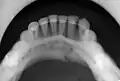

Panoramic radiography

Panoramic radiographs are tomograms where the mandible is in the focal trough and show a flat image of the mandible. Because the curve of the mandible appears in a 2-dimensional image, fractures are easier to spot leading to an accuracy similar to CT except in the condyle region. In addition, broken, missing or malaligned teeth can often be appreciated on a panoramic image which is frequently lost in plain films. Medial/lateral displacement of the fracture segments and especially the condyle are difficult to gauge so the view is sometimes augmented with plain film radiography or computed tomography for more complex mandible fractures.